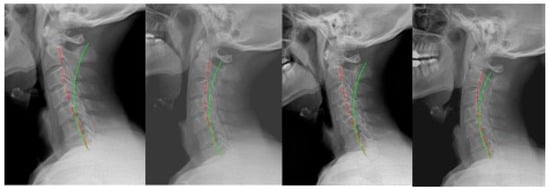

2.1. Case 1

2.2. Case 2

2.3. Case 3

2.4. Case 4